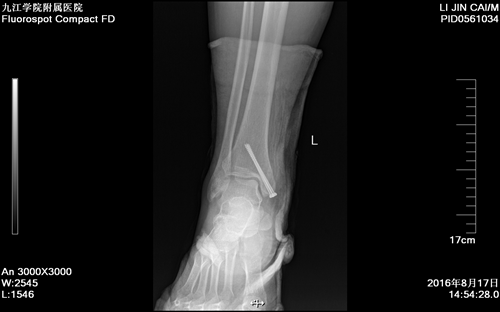

近日,临床医学院/附属医院骨三科成功为一名左侧内踝骨折患者行关节镜监视下左侧内踝骨折闭合复位螺钉内固定术。患者术后恢复良好,疼痛明显缓解,手术效果显著,标志着临床医学院/附属医院关节镜微创技术跃上新的台阶。

今年36岁的李某左踝部不慎被铲车车轮碾压,且全身多处挫伤,送往临床医学院/附属医院急救,收治于骨三科住院,诊断为左侧内踝骨折。经讨论后骨三科朱述浪主任决定采用在关节镜监视下行左侧内踝骨折闭合复位螺钉内固定术。手术过程顺利,术中骨折复位成功,填补了临床医学院/附属医院踝关节手术领域的空白。

术后复查X线片显示患者骨折复位良好,螺钉位置佳